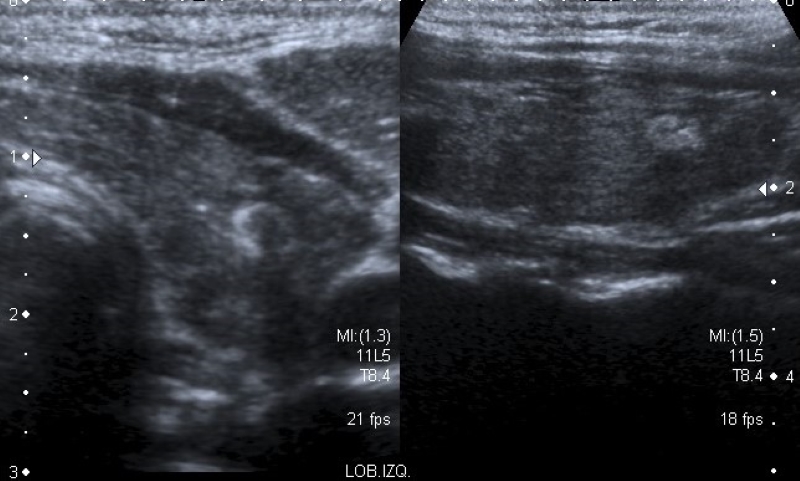

Márgenes

Es el borde entre el nódulo y el parénquima tiroideo adyacente o las estructuras extratiroideas. Se clasifican en “lisos” (Fig. 4) cuando son bien definidos, curvilíneos, de forma esférica o elíptica y no presentan interrupción en su extensión; “irregulares” (Fig. 5) cuando son espiculados o dentados, y puede dibujarse todo el contorno, lo que los diferencia de los “mal definidos” (Fig. 6), en los cuales es difícil distinguir adecuadamente del parénquima tiroideo. Se denominan “lobulados” (Fig. 7) cuando presentan protrusiones redondeadas y de diferentes tamaños. El “halo” (Fig. 8) es un anillo hipoecoico que rodea al nódulo, y puede rodearlo en forma parcial o completa. Este se considera una cápsula fibrosa que se observa más comúnmente en nódulos benignos, aunque también puede estar presente en algunos nódulos malignos2,18. En la literatura publicada, la mayoría de los autores mencionan que el tipo de márgenes que más frecuentemente se asocia a malignidad son los irregulares1,2,12,15,19,20,21,22, mientras que otros autores indican a los mal definidos16,23) como característica de malignidad.